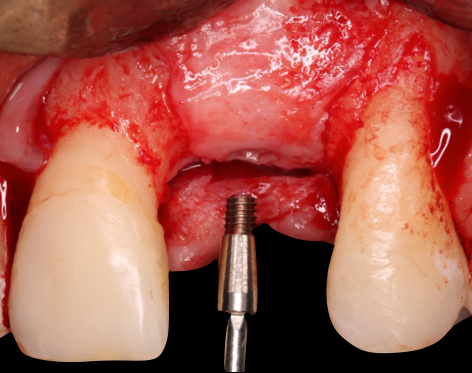

Após 6 meses de regeneração óssea guiada e mais 2 meses de processo de osseointegração tardia do implante, iniciamos a fase de reabertura e manejo do tecido com uma diferente abordagem de técnica de retalho (de Sanctis, 2014) com enxerto de tecido conjuntivo subepitelial (ETCS) removido da porção palatina da região do dente 21 onde havia um volume sobressalente proveniente da ROG, o mesmo foi estabilizado através de um cicatrizador com cinta de 3 mm e sutura colchoeiro horizontal. O manejo do tecido modifica o fenótipo gengival, proporciona estabilidade, reduz a recessão da margem periimplantar, proporciona um melhor contorno da crista alveolar e aumenta a espessura dos tecidos moles (Frizzera, 2018). Fig.5

Fig. 4A

Fig. 4B